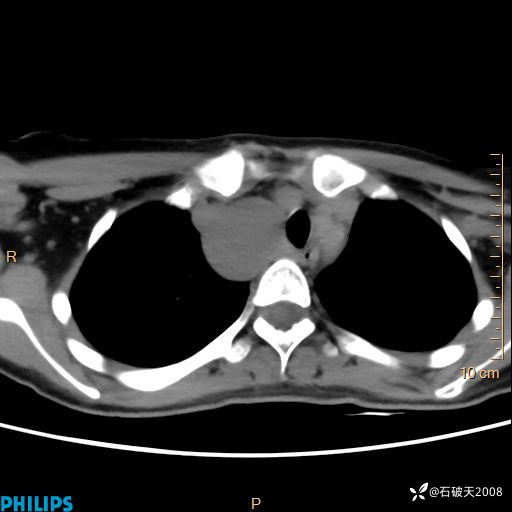

平扫